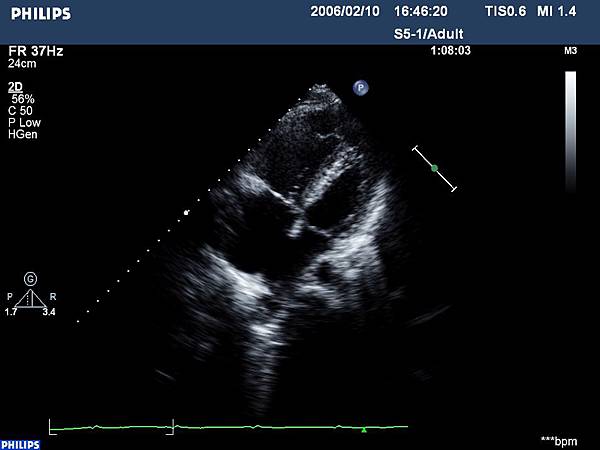

3. 有時候胸前心臟超音波不容易診斷:不要以為任何心臟的問題都可以用胸前心臟超音波確診!心房中膈的位置因為比較”後面”(遠離體表),再加上有些個體上的差異(特別是比較”壯碩”的人),做了超音波後卻無法確診的情形時有所聞。"不容易診斷"有兩種:一種是有破洞但是超音波看不出來,另一種是指其實本來沒有缺損,但超音波看起來卻很像有破洞。所以有些時候當診斷有疑慮時,需要其他影像檢查的輔助(例如經食道心臟超音波)。

當破洞並非小洞、但病人還完全沒有症狀時,醫師還是有辦法透過一些檢查來懷疑到這個疾病。在聽診時可能會有一些具有特色的心雜音、心電圖也會有一些特別的波行變化。當然,胸前心臟超音波還是不可或缺的診斷工具,若還是有診斷上的疑慮時,安排經食道心臟超音波幾乎就可以真相大白了。